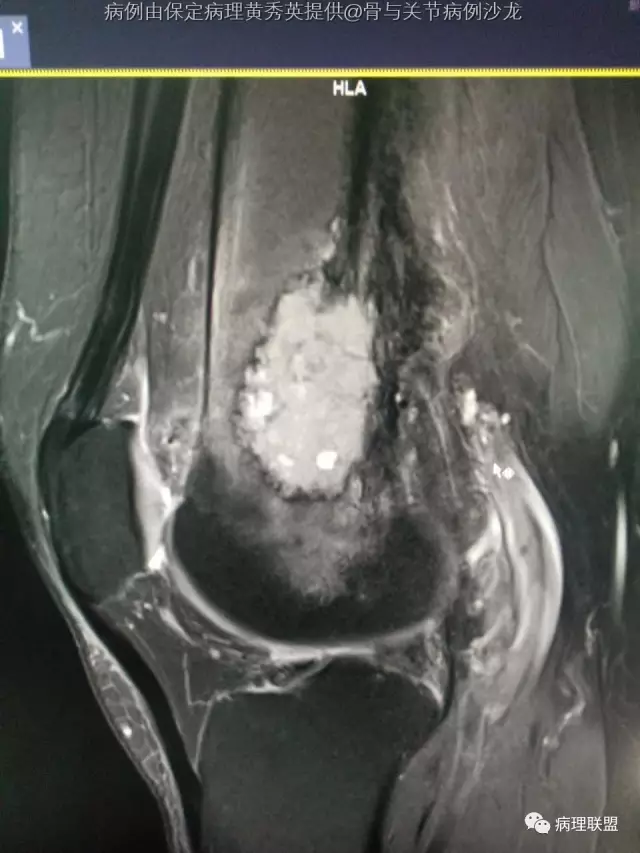

女67岁,股骨下端肿物约6cm,(病例由保定病理黄秀英提供,致谢!)